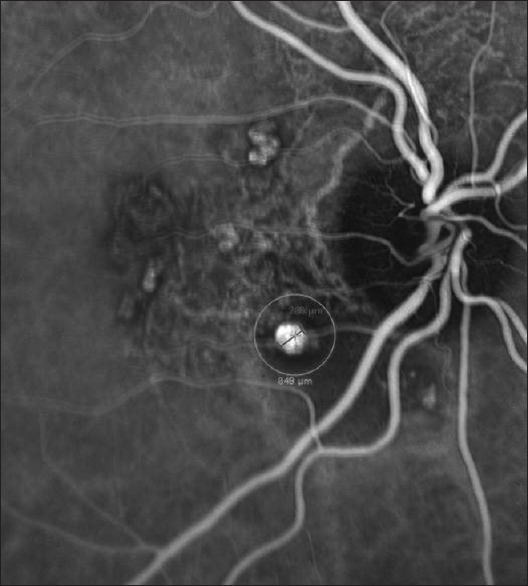

一位60岁的女性患有息肉样脉络膜血管病变(PCV),采用光动力疗法(PDT)治疗。治疗点很小(850µm),仅针对病变而不针对周围的血管网络。3天后,患者主诉视力严重受损,临床检查诊断为pdt所致急性渗出性黄斑病变(PAEM)。3天后的进一步检查一方面显示视网膜下积液已消退,但另一方面,确定PDT可能导致另外两个先前静止的PCV病变的激活。未应用其他治疗,并监测患者的临床状况。6周后复查,渗出现象完全消失,视力明显改善。三年过去了,病情依然稳定。我们的报告是文献中第一个描述PDT后小靶点(850µm) PAEM的病例,而没有其他报告表明pcv相关的PAEM可以在没有任何治疗的情况下自行消退。此外,PDT的应用伴随着两个先前不活跃的PCV病变的激活,这是先前未描述的不良反应。

A 60-year-old woman suffering from polypoidal choroidal vasculopathy (PCV) was treated with photodynamic therapy (PDT). The treatment spot was small (850 µm) and was targeted only against the lesion and not the surrounding vascular network. Three days later, she complained of severe visual impairment and the clinical examination set the diagnosis of PDT-induced acute exudative maculopathy (PAEM). Further examinations 3 days later demonstrated on the one hand that subretinal fluid had regressed, but on the other hand, it was identified that PDT possibly resulted in the activation of two other previously quiescent PCV lesions. No other treatment was applied, and the patient's clinical status was monitored. A new evaluation after 6 weeks, revealed the complete resolution of the exudative phenomena and the significant improvement of vision. Three years later, the condition remains stable. Our report is the first in the literature to describe a case of PAEM following PDT with a small target spot (850 µm), while no other report has demonstrated that PCV-associated PAEM may resolve spontaneously without any treatment. Moreover, the application of PDT was accompanied by the activation of two previously inactive PCV lesions, an adverse effect that has not been previously described.